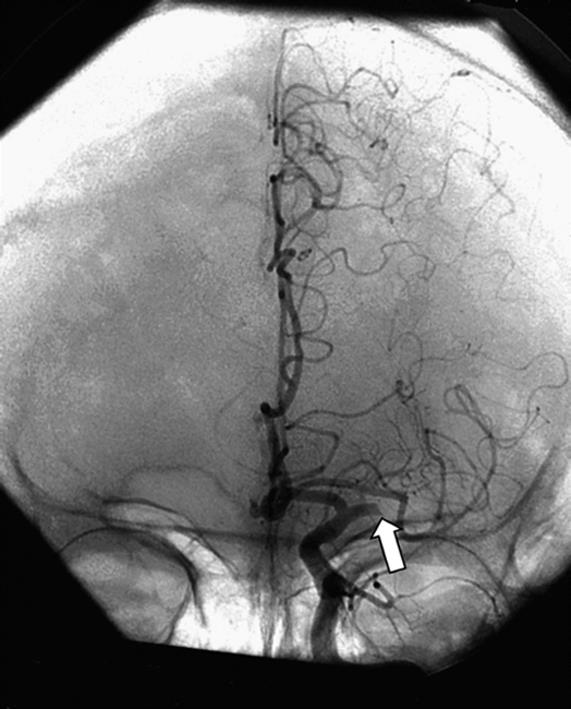

摘要:脉络膜前动脉动脉瘤(AChAA)是一种发生在脉络膜前动脉(AChA)及其与颈内动脉交界处的动脉瘤。AChAA的发生与发展受多种先天及后天因素影响,但其具体病因与流行病学特征缺少可靠的统计学证据。只依靠临床表现和一般检查无法确诊AChAA,需要影像学检查如CT血管造影、磁共振血管成像或数字减影血管造影证据。目前国际上对于有破裂风险的AChAA广泛采用开颅夹闭手术或血管内治疗,但是关于两种方式的治疗效果、并发症发生率以及预后仍存在争议。